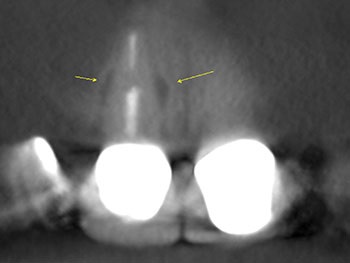

This patient was very worried that she was going to lose her front tooth, #8. Her dentist was concerned that the root had been split by a large, tapered post given the context of the bilateral radiolucencies located at the bottom of the post.

No crack was seen when the post was removed, nor were any lateral canals located. This tooth was treated in three visits over six months using a calcium hydroxide intracanal medicament. It is possible that a nidus of bacteria remained in the gap between the obturation and the post.

The patient’s symptoms resolved after the first visit. The case was obturated after confirming full bony healing. She is still extremely appreciative of the efforts made to save her front tooth.

Fig. 20: Preop CBCT.